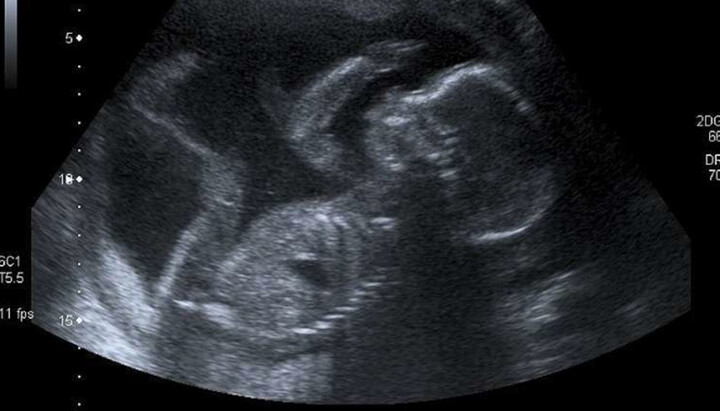

Ultraschall eines Kindes. Foto: EWTN NEWS Ultraschall eines Kindes. Foto: EWTN NEWS

In England und Wales haben Schwangerschaftsabbrüche einen historischen Höchststand erreicht. Den offiziellen Daten der Regierung zufolge wurden im Jahr 2019 insgesamt 209.519 Abbrüche registriert, die höchste jemals verzeichnete Zahl seit der Legalisierung durch den Abortion Act im Jahr 1967. Darüber berichtete EWTN News.